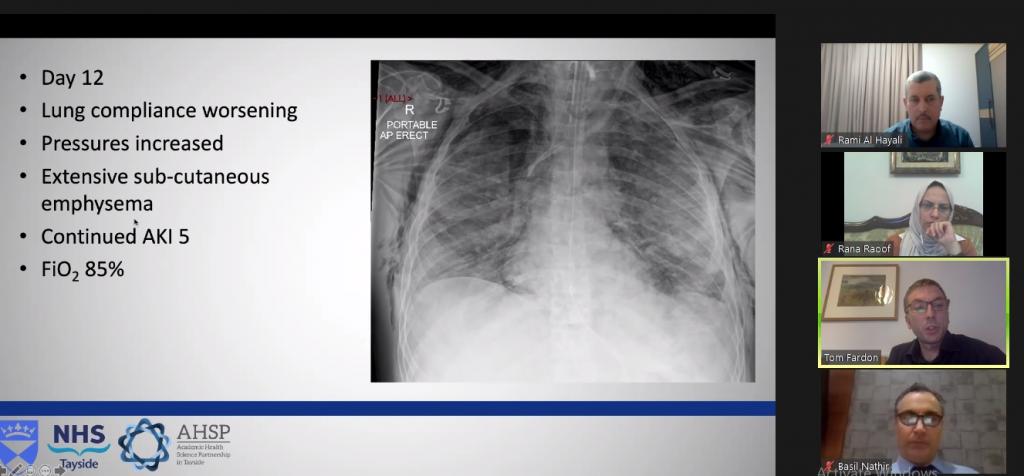

برعاية وحضور السيد عميد كلية الطب جامعة الموصل الأستاذ الدكتور باسل محمد نذير سعيد، والسيد المعاون العلمي الأستاذ المساعد الدكتور همام غانم ابراهيم، وبالتعاون مع شركة استرازينكا الدوائية، أقامت الكلية ندوتها العلمية الدولية الافتراضية الثالثة حول جائحة كورونا والموسومة: المستجدات حول طرق الوقاية والعلاج لجائحة كورونا Updates on Prevention and Treatment of COVID-19، وذلك يوم السبت 26 أيلول 2020. استُهِلَّت الندوة التي أدارتها بكفاءة مسؤولة شعبة الشؤون العلمية المدرس الدكتورة رنا ممتاز رؤوف بكلمة افتتاحية للسيد العميد، فكلمة تمهيدية لتدريسي فرع الطب الأستاذ المساعد الدكتور رامي محمد عادل الحيالي. بعد ذلك ابتدأت اعمال الندوة بمحاضرة الطبيب الاستشاري الدكتور توم فاردون (من اسكتلندا)، والموسومة: NHS Tayside Scotland – How We Dealt With COVID-19، ثم محاضرة الطبيب الاستشاري الدكتور مضر الخير الله (اسكتلندا)، والموسومة: The UK Handling of The COVID-19 Pandemic. بعد ذلك فُتح المجال للمناقشة والأسئلة والمداخلات من قبل الحضور. وقبيل الانتهاء، تفضل منسق الندوة الأستاذ المساعد الدكتور رامي محمد عادل الحيالي بكلمة الختام. وحضرَ الندوةَ عشرات الأساتذة والأكاديميين والمختصين من جامعات عراقية وعربية وعالمية مختلفة.